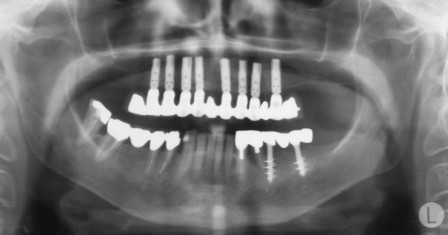

Riabilitazione superiore Implantoprotesi